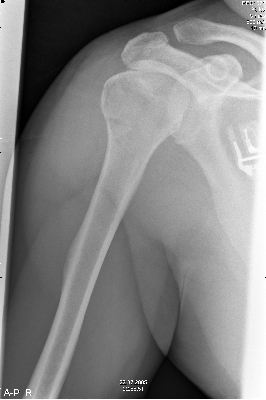

Nadat deze was terug gezet zag het er weer goed uit. |

|